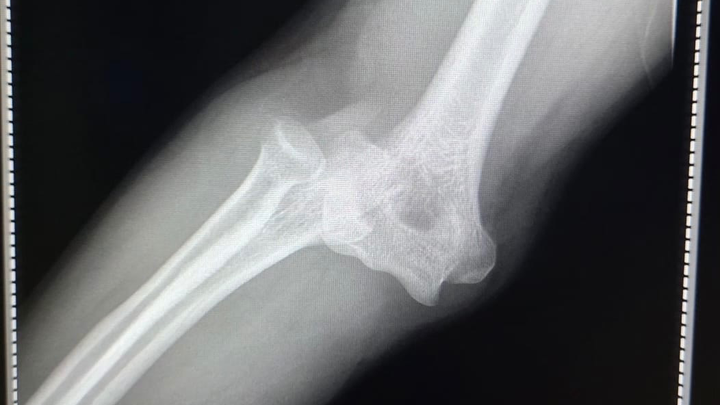

El día sábado sufrí una caída dislocándose mi codo derecho de una manera muy complicada para poder acomodarlo, tuve que viajar más de 5 hrs para poder encontrar atención médica capacitada para que realizaran la reducción (acomodo del hueso) pero al hacerlo se produjeron 2 fracturas, hasta hoy la cuenta médica asciende a $190,000 y sumando, ayúdenme a salir de esto.